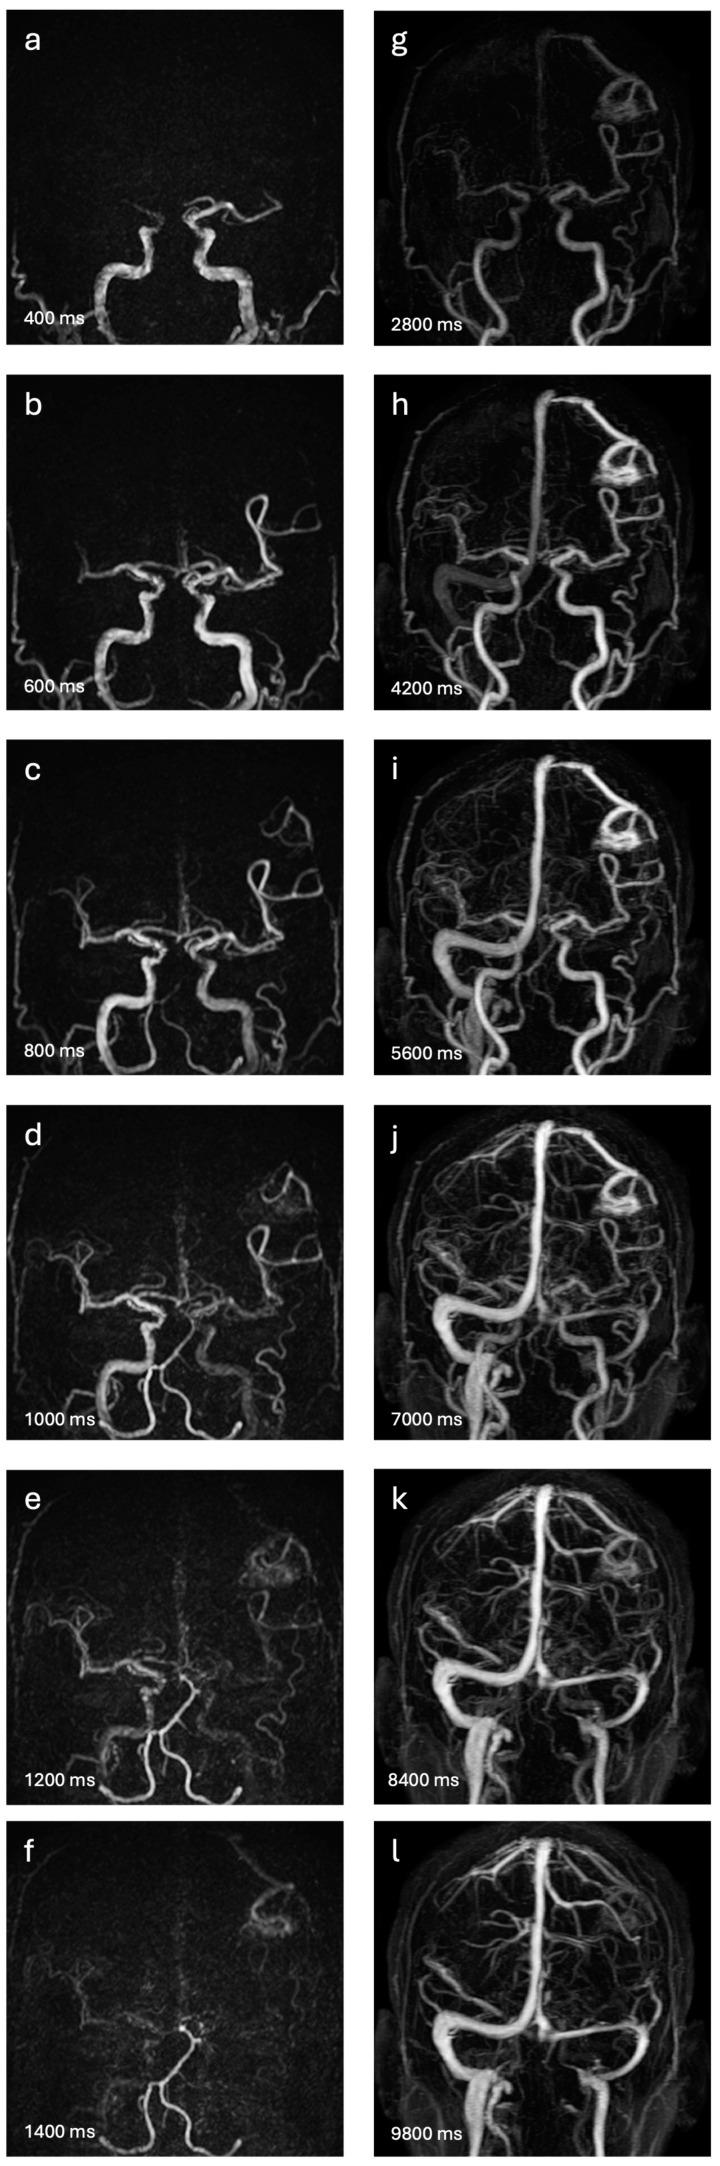

This study aims to assess the diagnostic accuracy of non-contrast-enhanced 4D MR angiography (NCE-4D-MRA) compared to contrast-enhanced 4D MR angiography (CE-4D-MRA) for the detection and angioarchitectural characterisation of brain arteriovenous malformations (bAVMs). Utilising a retrospective design, we examined 54 MRA pairs from 43 patients with bAVMs, using digital subtraction angiography (DSA) as the reference standard. Both NCE-4D-MRA and CE-4D-MRA were performed using a 3-T MR imaging system. The primary objectives were to evaluate the diagnostic performance of NCE-4D-MRA against CE-4D-MRA and DSA and to assess concordance between imaging modalities in grading bAVMs according to four main scales: Spetzler-Martin, Buffalo, AVM embocure score (AVMES), and R2eDAVM. Our results demonstrated that NCE-4D-MRA had a higher accuracy and specificity compared to CE-4D-MRA (0.85 vs. 0.83 and 95% vs. 85%, respectively) and similar agreement, with DSA detecting shunts in bAVMs or residuals. Concordance in grading bAVMs was substantial between NCE-4D-MRA and DSA, particularly for the Spetzler-Martin and Buffalo scales, with CE-4D-MRA showing slightly higher kappa values for interobserver agreement. The study highlights the potential of NCE-4D-MRA as a diagnostic tool for bAVMs, offering comparable accuracy to CE-4D-MRA while avoiding the risks associated with gadolinium-based contrast agents. The safety profile of imaging techniques is a significant concern in the long-term follow up of bAVMs, and further prospective research should focus on NCE-4D-MRA protocol improvement for clinical use.

本研究旨在评估非增强4D磁共振血管造影(NCE - 4D - MRA)与增强4D磁共振血管造影(CE - 4D - MRA)在检测和血管构筑特征描述脑动静脉畸形(bAVM)方面的诊断准确性。采用回顾性设计,我们检查了43例患有bAVM患者的54对MRA,以数字减影血管造影(DSA)作为参考标准。NCE - 4D - MRA和CE - 4D - MRA均使用3T磁共振成像系统进行。主要目的是评估NCE - 4D - MRA相对于CE - 4D - MRA和DSA的诊断性能,并根据四个主要量表(Spetzler - Martin、Buffalo、AVM栓塞评分(AVMES)和R2eDAVM)评估成像方式在bAVM分级中的一致性。我们的结果表明,与CE - 4D - MRA相比,NCE - 4D - MRA具有更高的准确性和特异性(分别为0.85对0.83和95%对85%),并且在DSA检测bAVM中的分流或残留方面具有相似的一致性。NCE - 4D - MRA和DSA在bAVM分级方面的一致性很高,特别是对于Spetzler - Martin和Buffalo量表,而CE - 4D - MRA在观察者间一致性方面显示出略高的kappa值。该研究强调了NCE - 4D - MRA作为bAVM诊断工具的潜力,在避免与钆基造影剂相关风险的同时,提供与CE - 4D - MRA相当的准确性。成像技术的安全性在bAVM的长期随访中是一个重要问题,进一步的前瞻性研究应侧重于改进NCE - 4D - MRA协议以供临床使用。